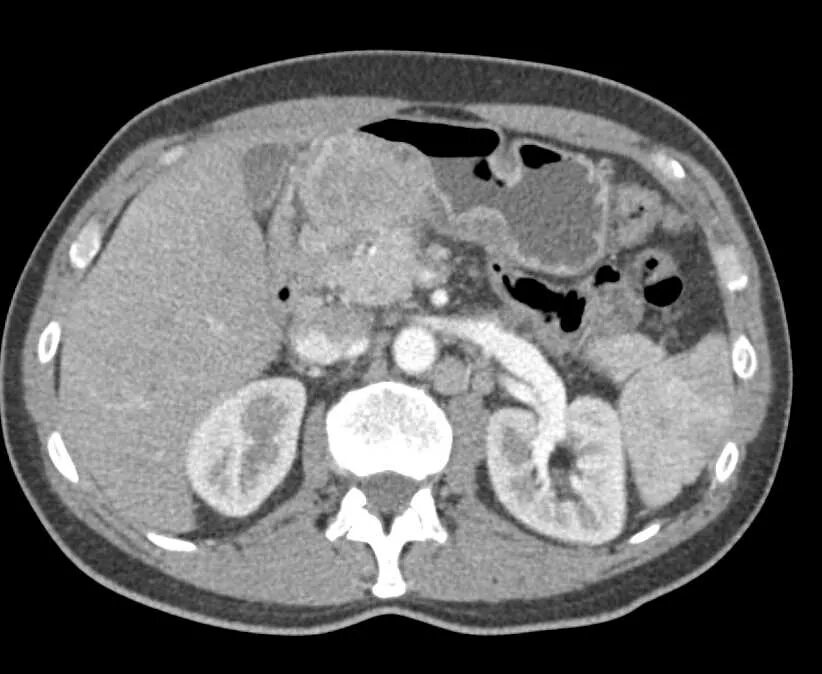

Язва желудка кт